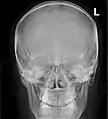

Paranasal sinuses seen in a frontal view

Paranasal sinuses are a group of four paired air-filled spaces that surround the nasal cavity.[1] The maxillary sinuses are located under the eyes; the frontal sinuses are above the eyes; the ethmoidal sinuses are between the eyes and the sphenoidal sinuses are behind the eyes. The sinuses are named for the facial bones and sphenoid bone in which they are located. Their role is disputed.